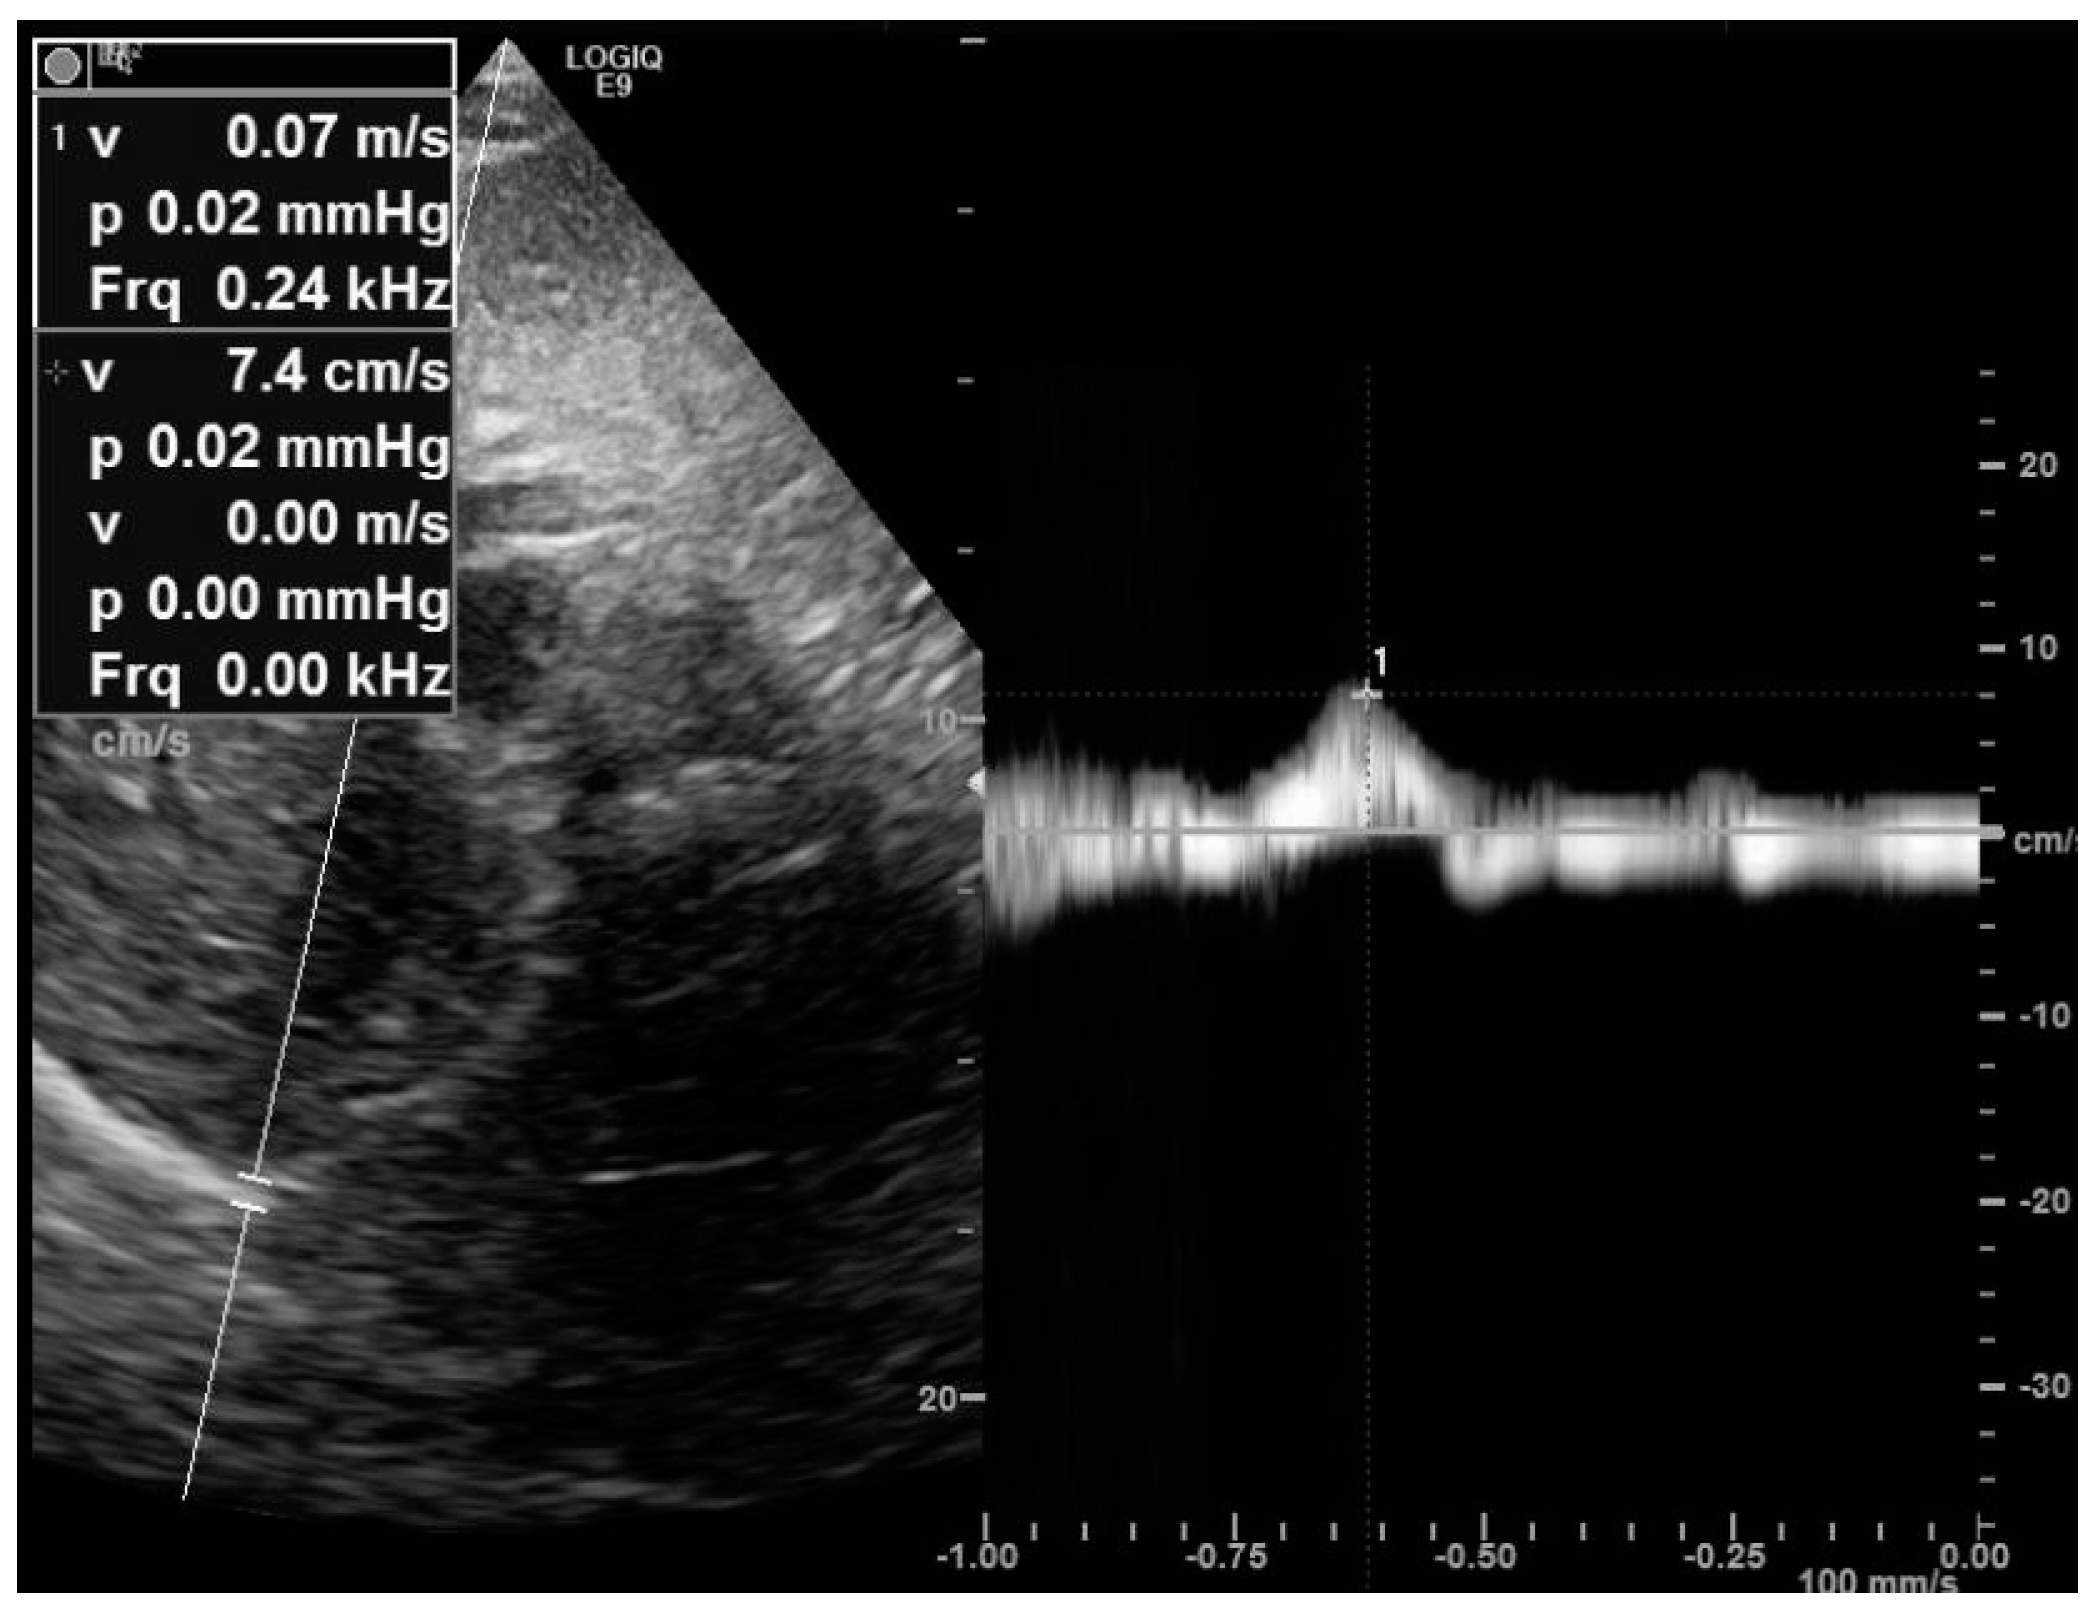

4.1. The Subcostal Approach

- Orde, S.R.; Boon, A.J.; Firth, D.G.; Villarraga, H.R.; Sekiguchi, H. Diaphragm assessment by two dimensional speckle tracking imaging in normal subjects. BMC Anesthesiol. 2016, 16, 43. [Google Scholar] [CrossRef]